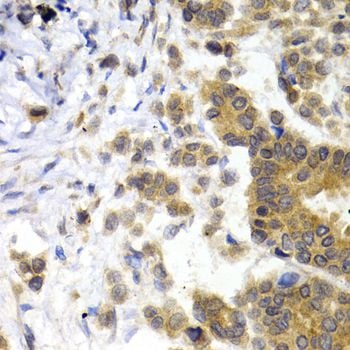

IHC (Immunohiostchemistry)

(Immunohistochemistry of paraffin-embedded human breast cancer using NEFL antibody at dilution of 1:200 (40x lens).)